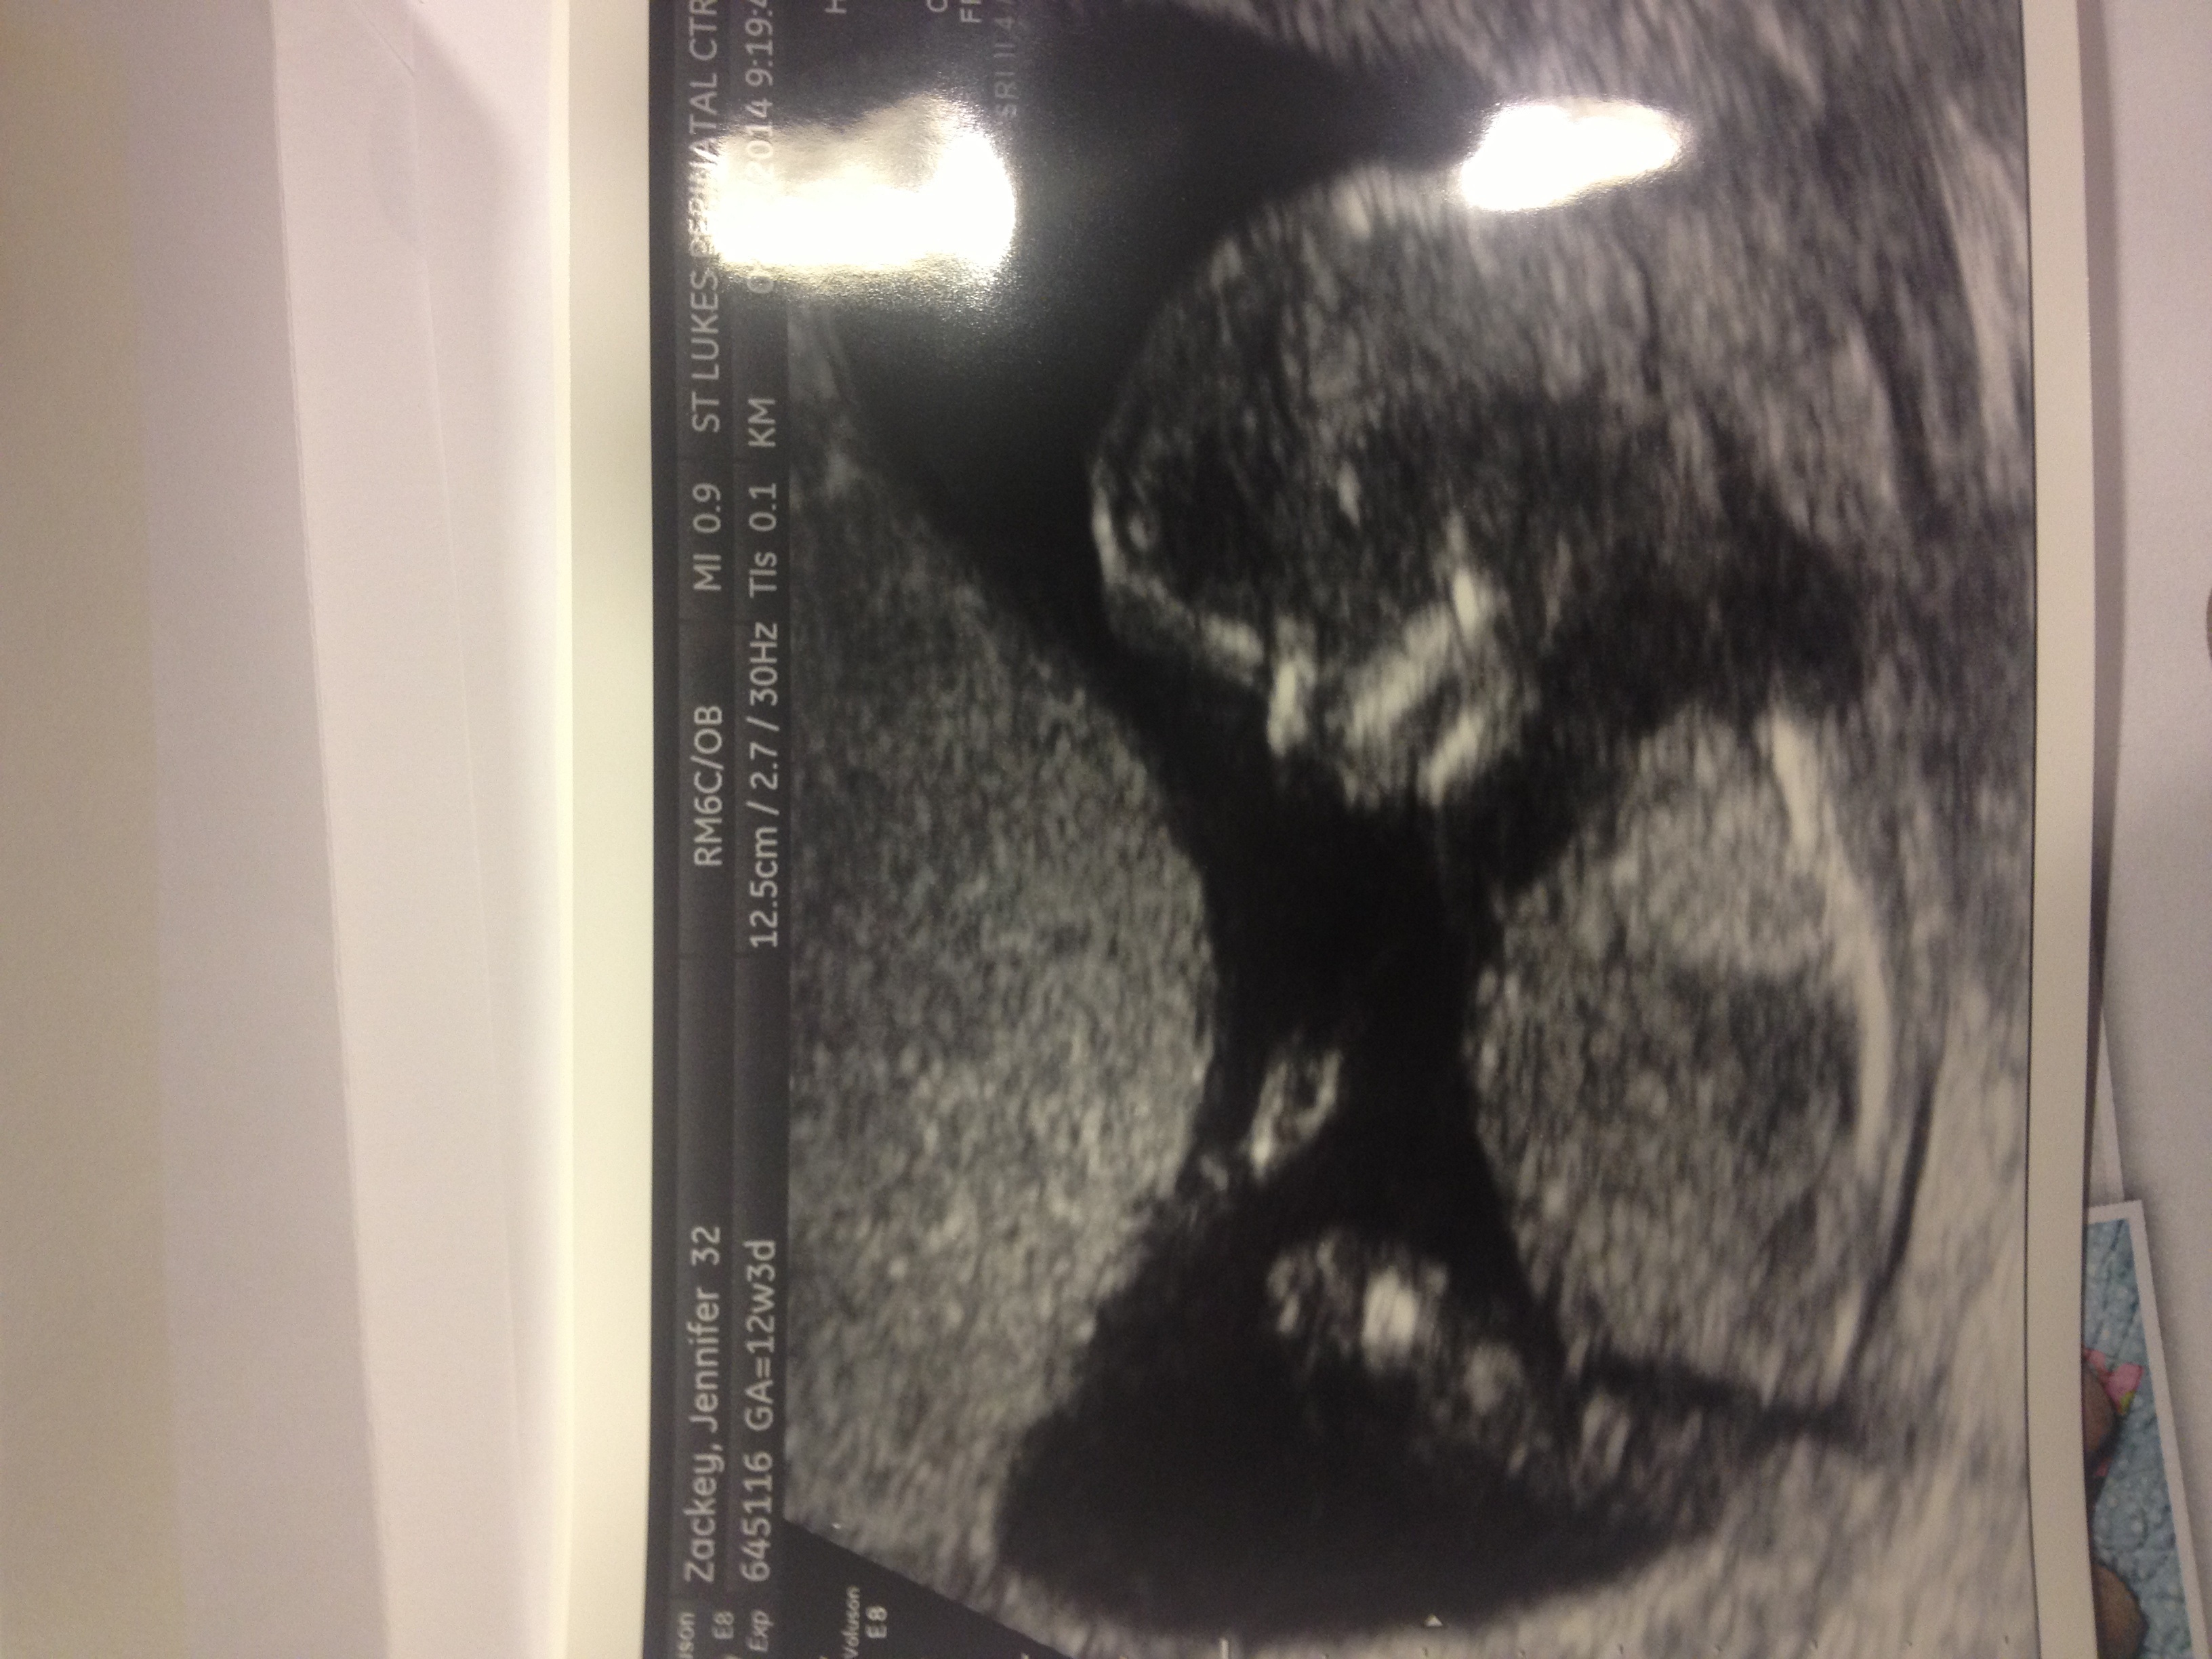

Attachment 17080

Someone told me that this is the nub. With the arrow pointing to it. Is that kinda long for nub? I guessed part of leg as well.

Any thoughts?

I'll admit freely that I'm not a sonographer, so it could be the nub, I just don't know. Any other nub-type scans?

yes, if that is the nub my guess is girl as well